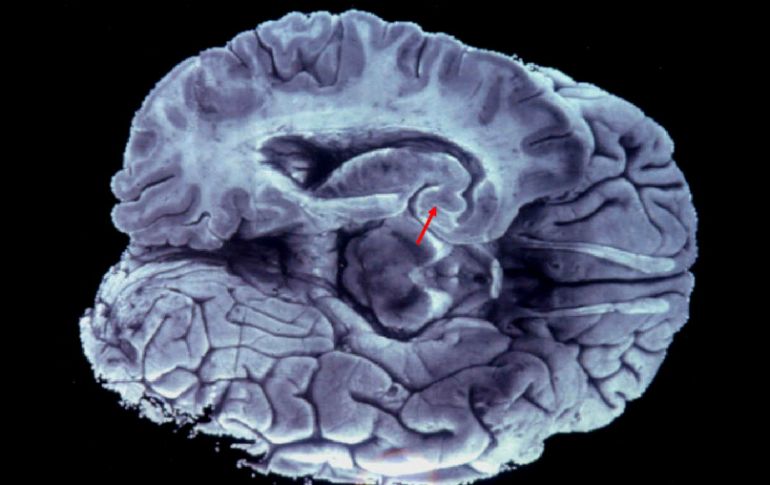

Suplementos | Muchas de las cosas que nos enseñan sobre nuestro cuerpo no son precisamente ciertas Mitos sobre el cuerpo humano Muchas de las cosas que nos enseñan sobre nuestro cuerpo no son precisamente ciertas Por: SUN 11 de septiembre de 2014 - 21:40 hs Durante mucho tiempo se creyó que sólo utilizábamos una décima parte de nuestro cerebro, siendo que utilizamos el cien. EFE ARCHIVO. / CIUDAD DE MÉXICO (11/SEP/2014).- Desde que somos pequeños, grandes cantidades de información llegan a nuestra mente, ya sea a través de la familia o al asistir a la escuela. Sin embargo, muchas de las cosas que nos enseñan no son precisamente ciertas. Sobretodo refiriéndose al cuerpo humano, del cual surgen mitos que siguen vivos aún después de haberse desmentido. -Tenemos sólo 5 sentidos. Cualquier niño pequeño te dirá que es cierto, que los cinco sentidos del ser humano son la vista, el olfato, el oído, el gusto y el tacto. De acuerdo a la Escuela de Medicina en Harvard, existen seis sentidos más en el cuerpo humano. Por ejemplo, cierra los ojos y luego toca tu nariz con el dedo índice. ¿Cómo supiste cuál era el dedo índice sin mirarlo? ¿Cómo saber dónde está tu nariz? ¿Oliste el dedo con tu nariz? ¿Acaso tu sentido del tacto te indicó cómo llegar a tu nariz a través de las moléculas del aire? Nada de eso, a eso se le llama propiocepción, que es el sentido encargado de informar la posición del cuerpo en relación a sí mismo. Otro de los sentidos que se mencionan, es la percepción temporal o el sentido del tiempo, que si bien parece sólo parte de nuestro lenguaje cotidiano, en realidad es de los más importantes, pues es el que se encarga de unirlos a todos. Una manzana, es sólo una serie de sensaciones diferentes sin el sentido del tiempo, que te dice que todo está pasando en el mismo momento. Basta con estar encerrado en una habitación, en completo silencio y el sentido del tiempo nos hará notar que estamos dejando pasar nuestra vida sin hacer nada. El sentido de equilibrio, llamado también la equilibriocepción y otros como: la termocepción, la interocepción y la nocicepción, los cuales puedes consultar en la página de la escuela de medicina en Harvard. -El mapa de la lengua. Probablemente recuerdes la clase en que te enseñaron que la lengua humana está trazada con una especie de mapa, en el que se localizan las áreas perceptivas de sabor. Por ejemplo, la teoría menciona que los sabores dulces se identifican solamente en la punta de la lengua y la percepción del resto de los sabores en otras áreas. La verdad es que el científico alemán D.P. Hanig, llevo a cabo una prueba de sabor en la que descubrió que algunos voluntarios experimentaron ciertos sabores con más intensidad en ciertas regiones de la lengua. Cuarenta años más tarde, un académico de Harvard, el Dr. Boring, interpretó mal los resultados de los estudios y el mapa que consideró como resultado, era simplemente el plan de trabajo para realizar la prueba. Actualmente, los investigadores han sabido por años que toda el área de la lengua es prácticamente igual de sensible a los diferentes tipos de sabores. - Utilizamos sólo el 10 por ciento de nuestro cerebro. Esta teoría que se le ha atribuido infundadamente a Albert Einstein, es uno de los mitos más antiguos sobre nuestro cuerpo. De acuerdo al British Medical Journal (BMJ), investigadores han aclarado que la mentira surgió en 1907, para argumentar el potencial de las personas de desarrollar múltiples talentos. La verdad es que utilizamos el 100 por ciento de nuestro cerebro. Especialistas señalan que las imágenes de resonancia magnética y estudios del metabolismo cerebral, demuestran que durante el día no queda ninguna parte del cerebro sin ser activada. Lo importante es fomentar la actividad cognitiva y cerebral desde la infancia, porque eso mantiene y aumenta las conexiones cerebrales. -Beber 8 vasos de agua al día. El consejo de beber 2 litros y medio de agua diarios se remonta a 1945, gracias a una recomendación del Consejo Nacional de Investigación de los Estados Unidos. Posteriormente en 1974, el nutricionista Frederick Stare, avaló el consejo sugiriendo consumir de seis a ocho vasos cada 24 horas. Sin embargo, se ha omitido la segunda parte de las recomendaciones, las cuales señalan que la mayor parte de los dos litros y medio de agua, se encuentran en los alimentos preparados y que, como aclara Stare, incluyen cualquier otro líquido como té, café, leche y cerveza, además del agua contenida en las frutas y verduras. De cualquier forma, hidratarse es fundamental para el buen funcionamiento del cuerpo, pues perdemos diariamente cerca de un litro de agua, que debe reponerse para la actividad del metabolismo. - Leer con luz tenue puede causar ceguera. De acuerdo a información del NY Times, leer con poca iluminación o a la luz de las velas, no causa pérdida de la visión, como nos enseñaron. Simplemente, la falta de luz puede crear la sensación de tener dificultades para enfocar y también reduce el parpadeo, lo que causa molestias, porque no se mantiene lubricado el ojo, pero esto no es un efecto que persista ni que dañe la visión. - La obesidad depende del metabolismo. Mucho se ha dicho que un metabolismo lento o acelerado, es la causa de que una persona tenga sobrepeso. La verdad es que de acuerdo a algunos científicos, el metabolismo es igual en personas delgadas y obesas, incluso se ha detectado que algunas personas sin sobrepeso, tienen un metabolismo más lento que otras que padecen de obesidad. Lo que realmente causa que una persona suba de peso, es que no se mantiene un equilibrio entre las calorías que consume y las que quema. -La personalidad se define por el lado del cerebro dominante. Nada es más falso que decir que una persona es más creativa o más analítica porque utiliza más determinado lado del cerebro. La masa cerebral, sí tiene algunas estructuras especializadas que se encargan de realizar determinadas funciones, pero no se agrupan en un lado específico. Los científicos afirman que para ser verdaderamente creativos o analíticos, es necesario tomar recursos de ambos lados del cerebro. Por otro lado, personas que han tenido que someterse a una cirugía donde se les extrae un hemisferio completo del cerebro, no pierden del todo su lado creativo o lógico. Incluso por lo general, recuperan una buena parte de las funciones que supuestamente corresponden a la parte extraída. - El pelo y las uñas siguen creciendo aún después de la muerte. Este es un mito que incluso algunas personas que han tenido contacto con cadáveres aseguran es cierto. Sin embargo, el médico forense, William Maple, en un artículo de BMJ, asegura que el crecimiento del pelo y de las uñas requiere una compleja regulación hormonal, que no se mantiene después de la muerte. La realidad es que los tejidos blandos se deshidratan, lo que puede llevar a la retracción del cuero cabelludo o de la piel alrededor de las uñas. Esto crea la apariencia de que han crecido, pero sólo es el contraste provocado entre los tejidos blandos encogidos y las uñas o el pelo. -Afeitarse provoca que el pelo crezca más grueso y oscuro. Seguramente muchas veces has escuchado esto, y hasta recibido el consejo de depilarse. Pero dermatólogos y estudios que datan de 1928, aseguran que el afeitarse remueve solamente la parte muerta del vello y no la sección viva que está bajo la piel, por lo que es improbable que se afecte el ritmo del crecimiento. En realidad lo que se elimina, es sólo la punta, que es más delgada y por eso al salir pareciera ser más grueso y duro. Además, agregó que como el vello nuevo no ha sido sometido a la luz solar o a la exposición de químicos, al surgir aparenta ser más oscuro. - La mayor parte del calor corporal se pierde por la cabeza. En algunas partes del mundo, sobretodo en las que el clima frío es más frecuente, se dice mucho que es bueno cubrirse bien la cabeza, porque el cuerpo pierde calor a través de ella. En realidad tapar la cabeza tiene tanto efecto como en cualquier otra parte del cuerpo. El mito surgió en la década de los 50, cuando el ejército de los Estados Unidos, realizando unas pruebas de supervivencia en climas fríos, cubrió a sus soldados en todas las partes del cuerpo, menos en la cabeza; obviamente esto aceleró la pérdida del calor corporal. A raíz de esto, se imprimió un manual de supervivencia, en el cual se aconsejaba abrigar la cabeza porque se perdía del 40 al 45 por ciento del calor interno a través de ella. Temas Ciencia médica Calor de hogar Mitos y leyendas Lee También INAPAM: ¿Cómo solicitar un turno para consulta médica gratuita? Nobel de Química premia el desarrollo de estructuras metal-orgánicas ¿Cómo quitar el mal olor de los zapatos de manera natural? Nobel de Física para Clarke, Devoret y Martinis por descubrimiento sobre fenómenos cuánticos Recibe las últimas noticias en tu e-mail Todo lo que necesitas saber para comenzar tu día Registrarse implica aceptar los Términos y Condiciones